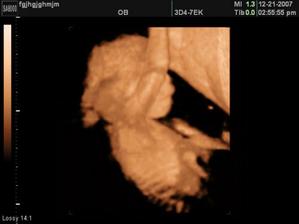

Moje holčička Sofinka

Sofinka pro všechny velkým překvapením, je to neplánované ale velice chtěné miminko.